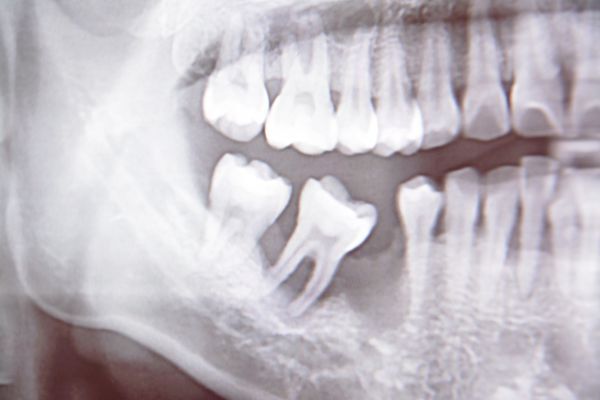

貼心的護士教導完刷牙步驟還特別幫我照X光

看看我傾斜的牙齒未來可以如何矯正

在矯正前可以注意哪些問題

而且透過治療陳醫師還提醒我右後側缺了多年的臼齒已有歪斜現象

假如不盡快做正畸治療恐怕未來要做植牙會有困難

且易影響牙齒清潔與咬合問題